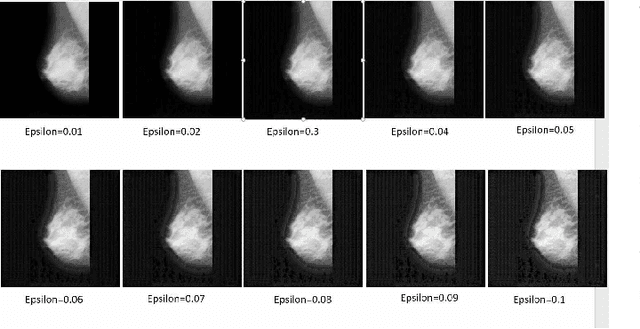

Artificial intelligence (AI) has been a topic of major research for many years. Especially, with the emergence of deep neural network (DNN), these studies have been tremendously successful. Today machines are capable of making faster, more accurate decision than human. Thanks to the great development of machine learning (ML) techniques, ML have been used many different fields such as education, medicine, malware detection, autonomous car etc. In spite of having this degree of interest and much successful research, ML models are still vulnerable to adversarial attacks. Attackers can manipulate clean data in order to fool the ML classifiers to achieve their desire target. For instance; a benign sample can be modified as a malicious sample or a malicious one can be altered as benign while this modification can not be recognized by human observer. This can lead to many financial losses, or serious injuries, even deaths. The motivation behind this paper is that we emphasize this issue and want to raise awareness. Therefore, the security gap of mammographic image classifier against adversarial attack is demonstrated. We use mamographic images to train our model then evaluate our model performance in terms of accuracy. Later on, we poison original dataset and generate adversarial samples that missclassified by the model. We then using structural similarity index (SSIM) analyze similarity between clean images and adversarial images. Finally, we show how successful we are to misuse by using different poisoning factors.